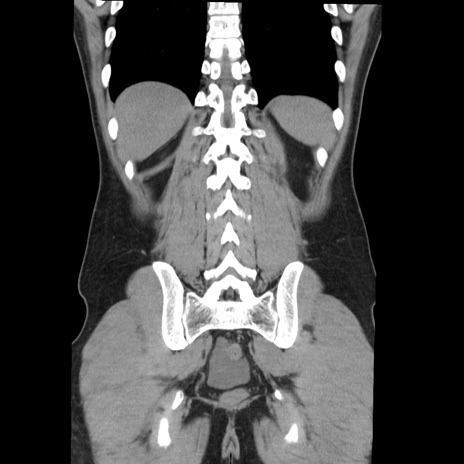

症例36(冠状断像)

【症例】20歳代 男性

【主訴】心窩部痛

【現病歴】今朝より上腹部痛あり。一旦軽快していたが再度出現したため救急要請。昨日夕に白身の魚を含む刺身を食べた。

【身体所見】BP 136/89mmHg、HR 74/min、BT 37.0℃、腹部:膨満、軟、心窩部に圧痛あり。反跳痛なし、筋性防御なし、腸雑音やや亢進あり。

【データ】WBC 17700、CRP 0.48